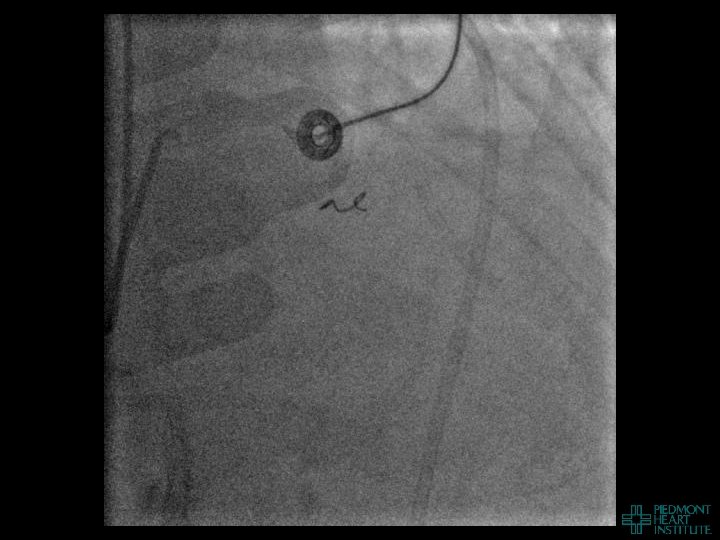

Case Example 4